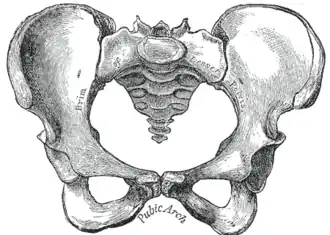

| Comparison between an android (left) and a gynecoid pelvis (right). | |

Traditional obstetrical services relied heavily on pelvimetry in the conduct of delivery in order to decide if natural or operative vaginal delivery was possible or if and when to use a cesarean section.[9] Women whose pelvises were deemed too small received caesarean sections instead of birthing naturally.

Traditional obstetrics have characterized four types of pelvises:

- Gynecoid: Ideal shape, with round to slightly oval (obstetrical inlet slightly less transverse) inlet.

- Android: triangular inlet, and prominent ischial spines, more angulated pubic arch.

- Anthropoid: the widest transverse diameter is less than the anteroposterior (obstetrical) diameter.

- Platypelloid: Flat inlet with shortened obstetrical diameter.